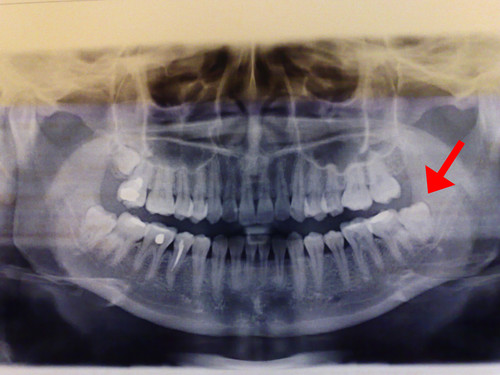

普通智慧齒,如下圖:

在深圳維港歡樂口腔掹此類智慧齒一般需要10分鐘左右的時間。